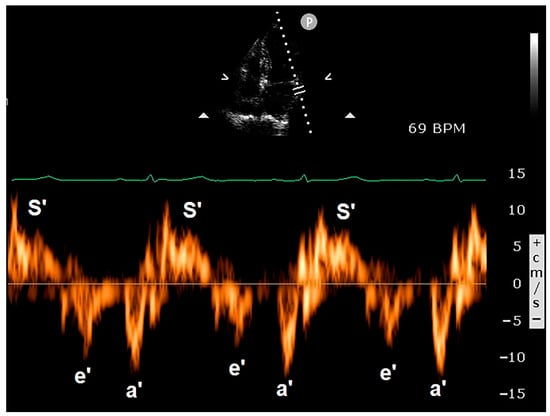

Figure 5 illustrates representative examples of PW-TDI assessment of RA pseudomasses.

Figure 5.

Examples of PW-TDI assessment of the systolic infolding of the lipomatous right atrioventricular junction (A) and of the RA infero-lateral wall (B). Spectral PW-TDI allows for the detection of a pattern of concordant motion in synchrony with the phases of the cardiac cycle, thus indicating RA pseudomasses. PW, pulsed wave; RA, right atrial; TDI, tissue Doppler imaging.

The use of PW-TDI for evaluating LV function was first reported by Isaaz et al. in 1989 [80]. The authors validated this innovative, non-invasive method for assessing the motion dynamics of the left ventricular (LV) posterior wall. In current clinical practice, PW-TDI is primarily used to quantify myocardial velocities throughout the cardiac cycle. For this purpose, the ultrasonographic system should be optimized to filter out the high-velocity signals of blood flow within the cardiac chambers and display only the low-velocity and high-amplitude signals of the wall motion velocities [81]. Regional quantification of myocardial velocities can be carried out at selected sites in either parasternal or apical windows. A small sample volume (usually 5 mm axial size) is used for accurate placement within the myocardium, whereas sampling cannot be localized to the endocardial or epicardial layers. Typically, in order to assess the regional systolic and diastolic myocardial velocities in the lateral and septal segments, a pulsed Doppler sampling is performed from the apical four-chamber view in the basal regions of the left ventricle adjacent to the mitral annulus [82]. Measurement of myocardial velocities from the apical views with PW-TDI reflects the LV longitudinal shortening and relaxation. On the other hand, velocities recorded in the parasternal views represent short-axis shortening and relaxation. Myocardial velocities recorded with PW-TDI have three main components over a cardiac cycle. These include a positive systolic wave (S’ velocity), which represents myocardial contraction, and two negative waves, which represent early diastolic myocardial relaxation (e’ velocity) and active atrial contraction in late diastole (a’), respectively (Figure 6).

Figure 6.

Spectral PW-TDI was obtained by placing the sample volume on the basal lateral wall of the left ventricle. The systolic wave (S’ velocity) represents myocardial contraction, while the two negative waves represent early diastolic myocardial relaxation (e’ velocity) and active atrial contraction in late diastole (a’), respectively. PW, pulsed wave; TDI, tissue Doppler imaging.